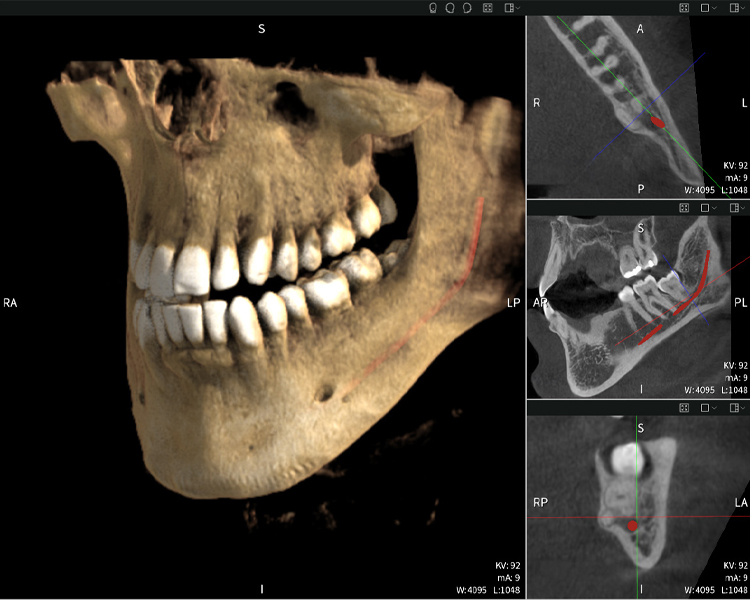

Figure b: Imaging results of Seethrough Max, in front of a black background.

Figure b

Figures b–d show various views of a 3D reconstruction of the mandible, providing a comprehensive overview of the mandibular anatomy, the position of the nerves in relation to the teeth, and allowing assessment of tooth symmetry and alignment.

Figure d shows the previously treated tooth 48, with its crown removed, and its roots left in proximity to the nerve, illustrating the high risk of nerve damage.